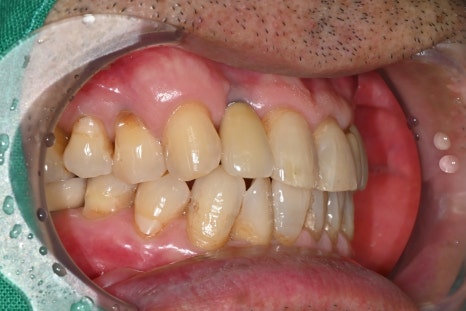

보철 제작과 최종 장착

마지막 단계에서는

환자의 교합에 맞는 보철물을 제작하여 장착합니다.

어금니 임플란트는 씹는 힘을

견뎌야 하기 때문에 정확한

교합 조정이 매우 중요합니다.

임플란트 치과에서는

교합을 여러 번 확인하며 미세 조정을 진행합니다.

치료 후 변화

임플란트는 단순한 치료가 아니라

삶의 질을 회복하는 시술입니다.

치료 후 환자분은

어금니로 음식을 편하게 씹을 수 있게 되었으며,

저작 기능 회복

통증 감소

잇몸 상태 안정

일상생활 개선

등의 변화를 경험하셨습니다.